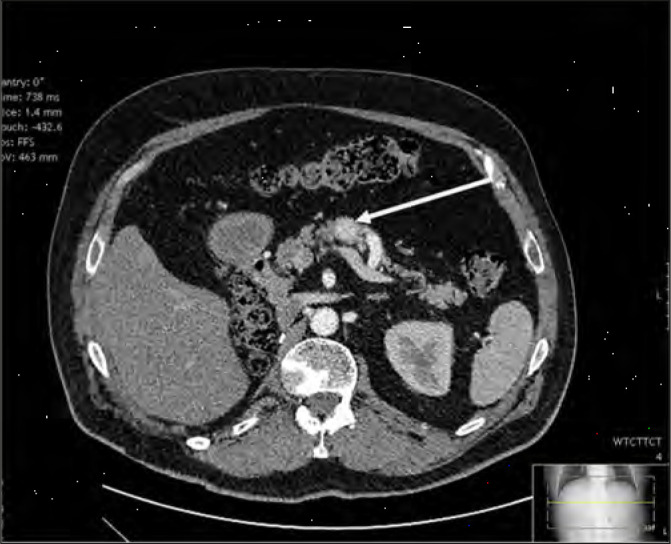

Abstract Image